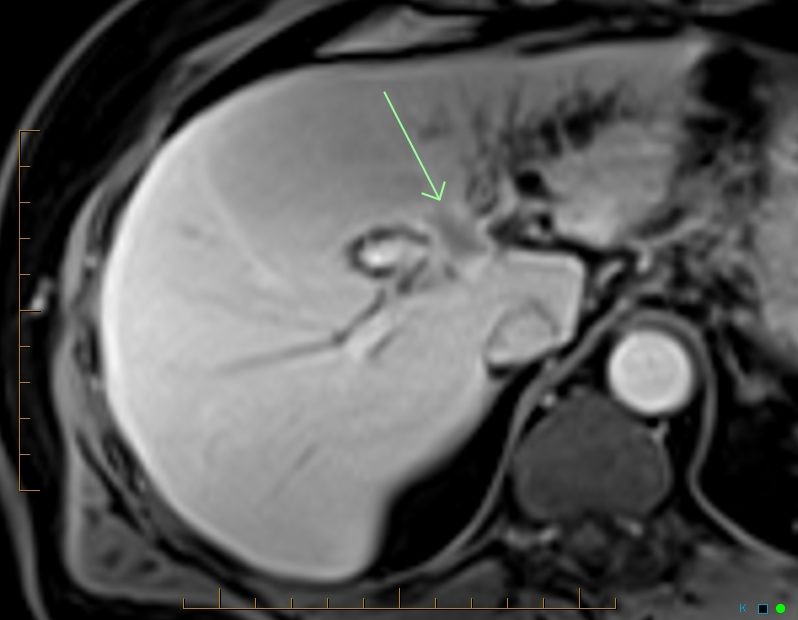

Colangiocarcinoma